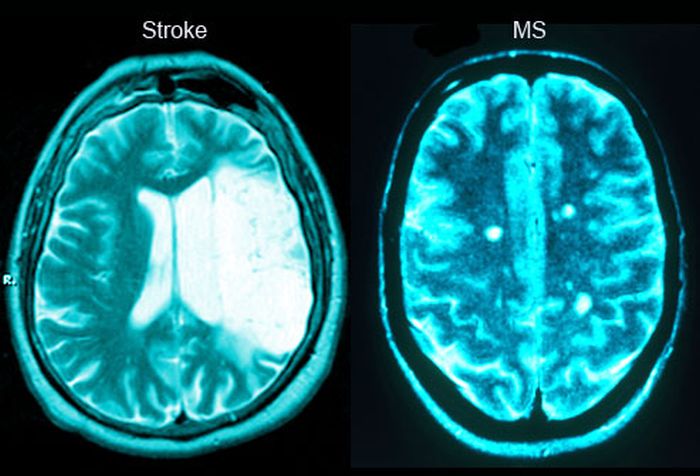

Η σύγχυση, οι δυσκολίες στην άρθρωση και η μυϊκή αδυναμία είναι τρία κοινά συμπτώματα που εκδηλώνονται στην περίπτωση σκλήρυνσης κατά πλάκας αλλά και μετά από εγκεφαλικό. Εάν εμφανιστούν ξαφνικά, πιθανότατα πρόκειται για εγκεφαλικό.